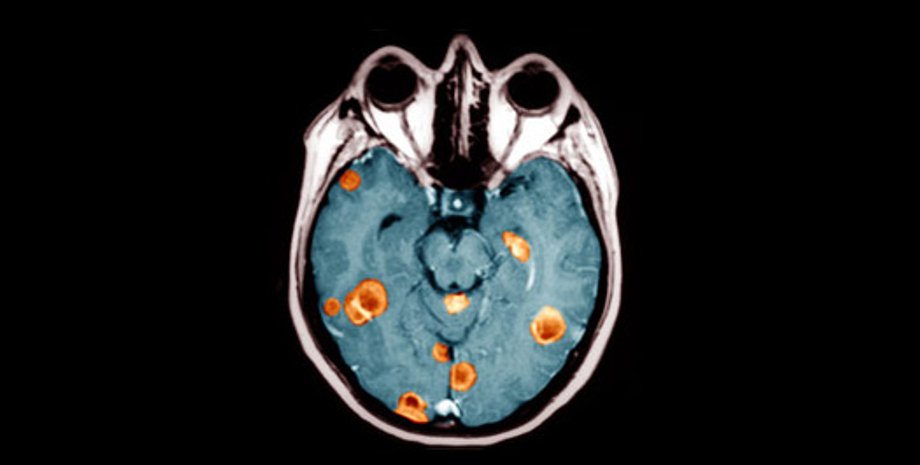

Ученые нашли гены, ответственные за возникновение рака мозга

Ученые из Колумбийского университета обнаружили два гена, ответственные за возникновение одной из наиболее быстро развивающихся форм рака головного мозга

Так называемая Glioblastoma multiforme в считанные месяцы приводит к развитию неоперабельной опухоли, однако до сегодняшнего дня медики не могли понять причину столь стремительного протекания заболевания.

Как сообщает cybersecurity.ru, исследование группы ученых указывает в качестве наиболее возможной причины пару генов: C/EPB и Stat3. Оба гена работают вместе, "запуская" генетическую цепочку, приводящую к превращению здоровых клеток мозга в раковые.

Как показали результаты исследования, все пациенты, у которых были задействованы оба эти гена, умерли в течение 140 недель после постановки диагноза.

В группе пациентов, у которых эти гены были неактивны, к этому моменту жив был каждый второй.

Руководитель исследования Антонио Иавароне говорит, что эти гены задают организму программу, выступая своеобразным катализатором образования опухоли.

"При одновременной активности они подключают к работе еще несколько сотен генов, превращающих здоровые клетки головного мозга в блуждающие", - пояснил Иавароне. "Наше открытие означает, что одновременное подавление активности обоих генов с помощью медицинских препаратов может быть мощным средством для пациентов, подходящего лечения для которых не существует", - добавил он.

В ходе эксперимента, поставленного генетиками, раковые клетки, пересаженные мышам, теряли способность к размножению, если предварительно ученые блокировали у них работу двух генов. Сейчас команда Колумбийского университета пытается разработать препарат, который давал бы тот же эффект.

По словам доктора Иавароне, открытие роли генов C/EPB и Stat3 в развитии рака стало для ученых полной неожиданностью - раньше об их участии в этом процессе даже не подозревали. "С терапевтической точки зрения это означает, что мы больше не должны тратить время, разрабатывая препараты для борьбы с факторами, минимально влияющими на развитие рака мозга - мы можем сразу приниматься за главную причину", - пояснил руководитель исследования.